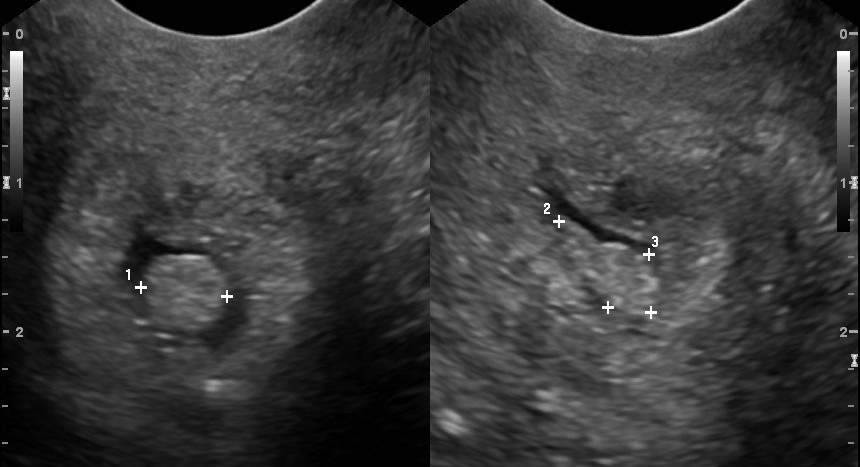

What pathology are we seeing in this image?

Nabothian cyst